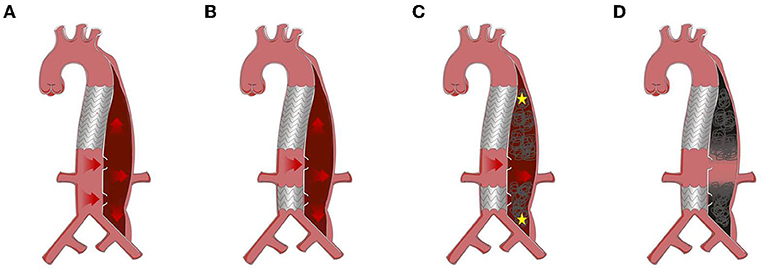

Figure 2. Protocol of road block strategy (RBS). (A) Distal dilatation of chronic aortic dissection in the visceral part (CADAV), red arrow represents blood flow direction. (B) Excluding tears away from visceral artery with covered stent. (C) False lumen (FL) embolism with coils, Onyx glue, or occluders, from the proximal and distal initial point (yellow asterisk) to the level of visceral arteries, preserving the blood flow to perfuse vital branches (red arrow). (D) Segmental thrombosis formed in the FL while visceral artery remained patent.